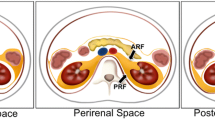

5.2 Retroperitoneal Space

The RP space is divided into four anatomically separate compartments [5]: the posterior pararenal space is encompassed by the posterior parietal peritoneum. The anterior pararenal space extends to the transversalis fascia [5]. The perirenal space is encapsulated by the perirenal fascia. The anterior pararenal space contains visceral organs that mainly originate from the dorsal mesentery, i.e., the pancreas and the descending and ascending parts of the colon. The perinephric space is bounded anteriorly by Gerota’s fascia and posteriorly by Zuckerkandl’s fascia [5]. It contains the kidneys and adrenal glands. The perinephric space is home to bridging septa and a network of lymphatic vessels, which may facilitate the spread of disease processes to or from adjacent spaces. The perinephric space is limited caudally by the merging of Gerota’s and Zuckerkandl’s fascias and therefore does not continue into the pelvic region [5]. The posterior pararenal space is bound by the transversalis fascia on its posterior face. Anatomic communication between the posterior pararenal space and the structures of the flank wall may be established. A fourth space surrounds the large vessels, the aorta, and the inferior vena cava. This space has a lateral boundary with the perirenal spaces and ureters and extends cranially into the posterior mediastinum [5]. Some diseases, for example, RP fibrosis, are largely limited to this space. Depending on the definition, some sources refer to a fifth space, which includes the muscular structures with psoas and quadratus lumborum muscles.